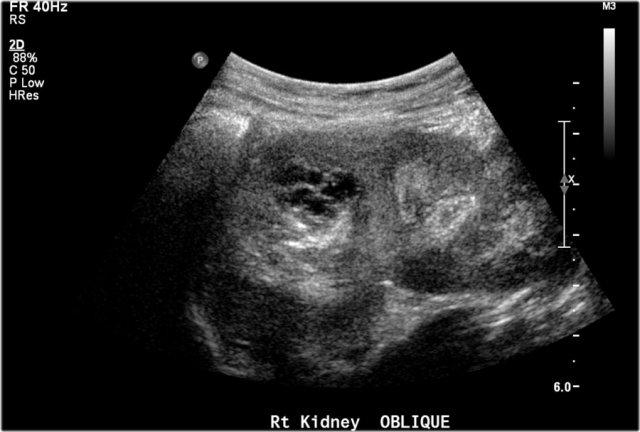

Hình ảnh của một bé trai 1 tháng tuổi được phát hiện MCKD trên siêu âm trước sinh.

Có thể thấy một ít mô thận và nhiều nang lớn.

Trên xạ hình thận với Tc-99-DMSA, không ghi nhận sự hấp thu ở phía bên trái.

Hình ảnh này phù hợp với bệnh thận đa nang loạn sản (MCKD).

Trước sinh, thận trái được chẩn đoán có hệ thống đôi kèm ứ nước thận. Siêu âm sau sinh cho thấy một nang lớn ở cực trên thận trái và một số nang nhỏ hơn (không hiển thị trong hình).

Không thấy nhu mô thận bình thường.

Trên chụp bàng quang – niệu đạo khi tiểu (MCUG), thấy hình ảnh trào ngược vào hệ thống cực dưới, bị đẩy xuống dưới và xoay do khối ở cực trên.

Đây nhiều khả năng là MCKD khu trú ở cực trên.

MCKD có thể ảnh hưởng đến một cực của hệ thống đài bể thận đôi.